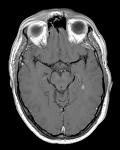

The McDonald criteria describe the steps to take to diagnose Multiple Sclerosis in different situations.

This e-learning will lead you through the criteria using several cases. By examining the cases you will be trained in using the McDonald criteria in the appropriate way in all possible situations. Each of the Cases describes an unique scenario such as Primary Progressive MS, a patient without MS etc etc. You're advised to run through the cases without further information by choosing a case from the menu above. (If you want to jump to a specific scenario make your choice here).